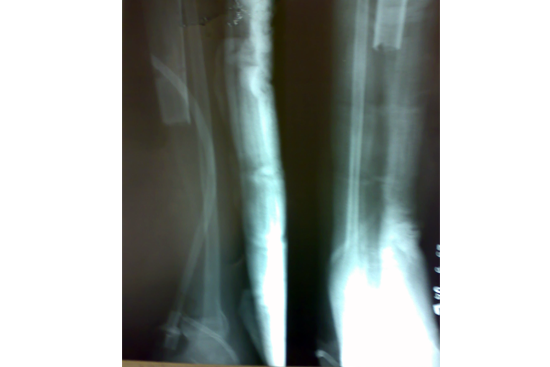

We have done Huntington technique by stage ilizarov procedure. Here is the diagrammatic representation of our method.